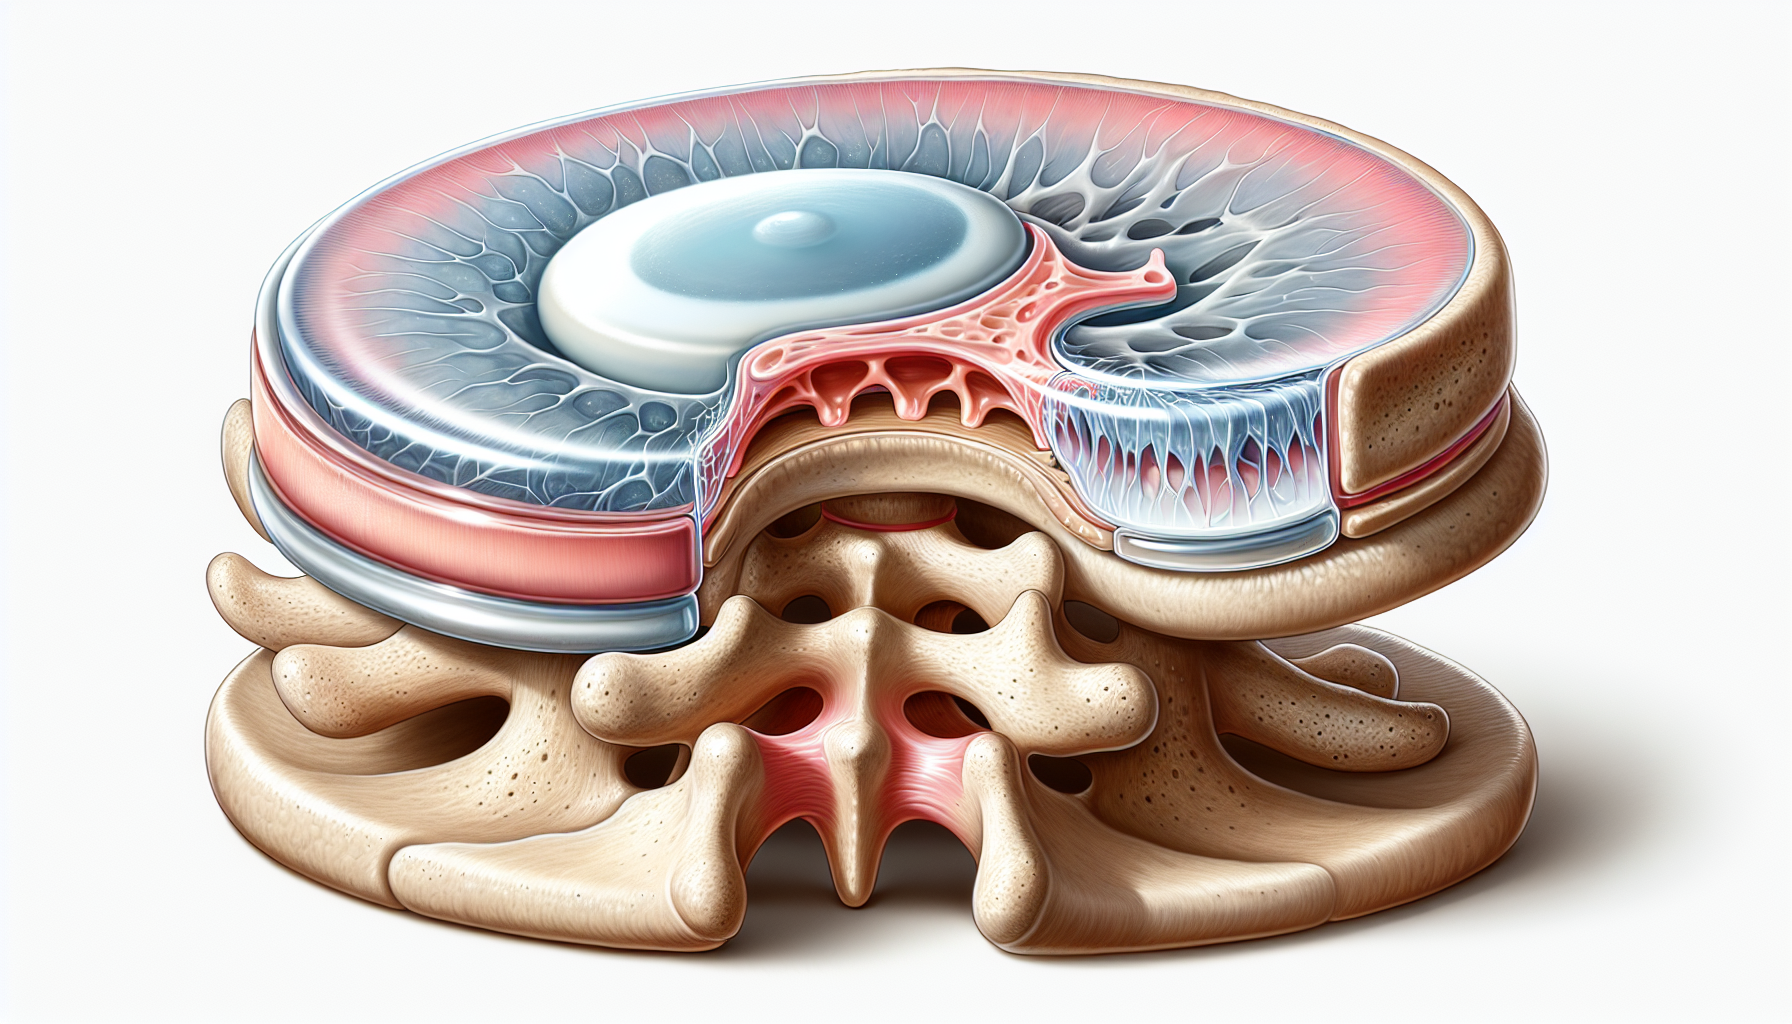

Comprendre le pincement discal Définition de la condition Le pincement discal se caractérise par une compression excessive d’un disque intervertébral, qui peut provoquer des douleurs aiguës et des limitations de mouvement. Cette condition est souvent le résultat d’une usure ou de blessures, et elle peut survenir dans n’importe quelle partie de la colonne vertébrale, mais est fréquemment observée dans les régions lombaires et cervicales. En conséquence, le pincement discal peut interférer avec la qualité de vie, rendant des activités quotidiennes simples extrêmement difficiles.

Types de douleurs et mécanismes sous-jacents Les douleurs causées par le pincement discal peuvent être classées en plusieurs catégories. La douleur nociceptive, par exemple, résulte d’une irritation des tissus mous environnants. Parallèlement, les douleurs neuropathiques peuvent se manifester si les nerfs adjacent au disque sont compressés. Ces mécanismes jouent un rôle crucial dans la manière dont chaque patient ressent sa douleur. Des traitements rapides et efficaces sont essentiels pour éviter que cette douleur ait des répercussions trop profondes sur la vie quotidienne.